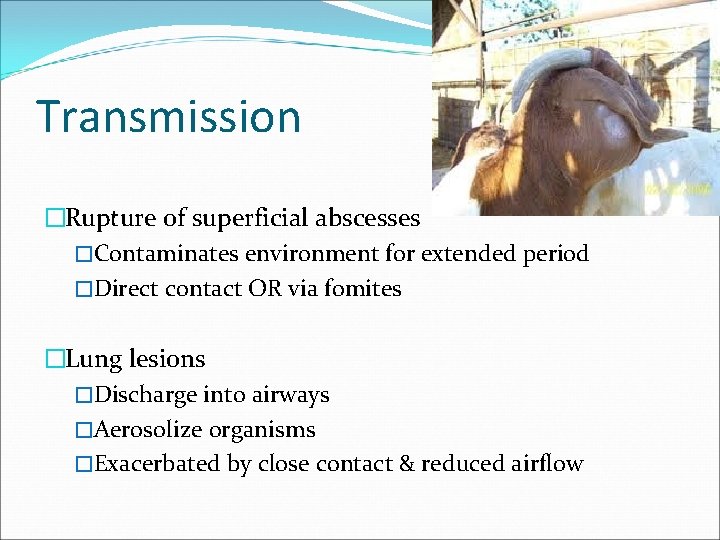

Transmission �Rupture of superficial abscesses �Contaminates environment for extended period �Direct contact OR via fomites �Lung lesions �Discharge into airways �Aerosolize organisms �Exacerbated by close contact & reduced airflow

Transmission: Introduction of Infection �Naïve flock/herd �#1: Clinically or subclinically infected carrier animal �Fomites � Farm workers/shearers � Shearing equipment � Portable handling equipment � Hay? ?

Risk Factors �Minor skin damage from shearing �Increased if plunge/shower dipping done w/in few days �Close confinement �Increasing age �Dusty environment